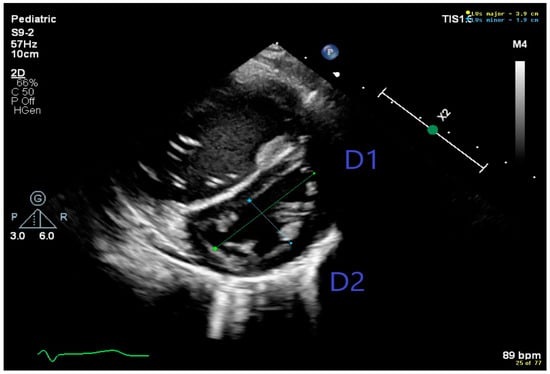

3.3. Diagnosis of Bronchopulmonary Dysplasia Associated Pulmonary Hypertension (BPD-PH)

- Revanna, G.K.; Kunjunju, A.; Sehgal, A. Bronchopulmonary dysplasia associated pulmonary hypertension: Making the best use of bedside echocardiography. Prog. Pediatr. Cardiol. 2017, 46, 39–43. [Google Scholar] [CrossRef]